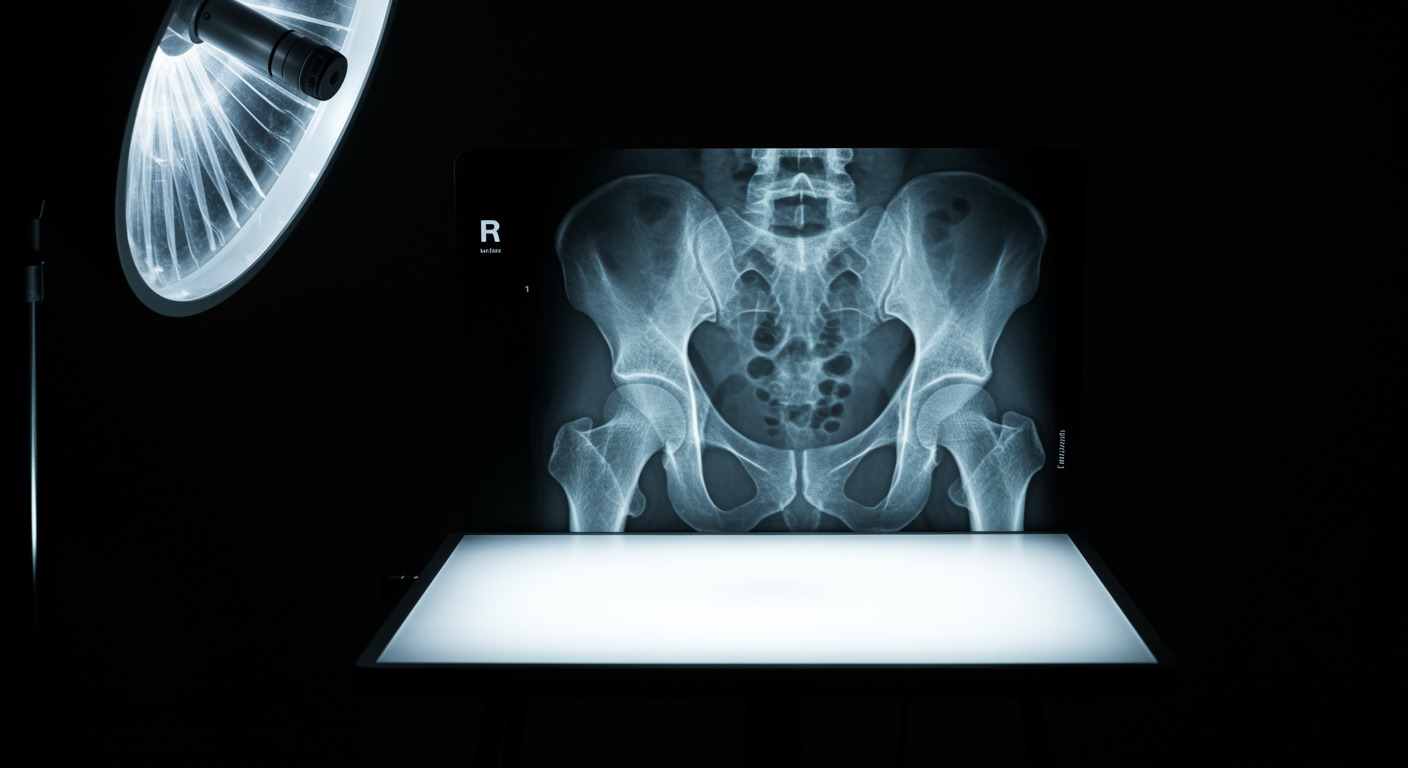

Does Stopping Hormone Therapy Increase Fracture Risk?

Yes, significantly. This large prospective study found that women who stopped hormone therapy had a 55% increased risk of hip fracture within 3-5 years compared to those who continued treatment. The protective bone effects of hormone therapy are lost relatively quickly after discontinuation, making transition planning crucial for women who need to stop treatment.

The study followed over 93,000 postmenopausal women in a large health management organization, tracking hip fracture rates among current users, past users, and never-users of hormone therapy. Women who stopped hormone therapy had hip fracture rates of 2.3 per 1,000 person-years compared to 1.5 per 1,000 for continuing users. The increased risk became apparent within 3 years of discontinuation and persisted for at least 5 years, suggesting that the bone protective effects are lost relatively quickly.